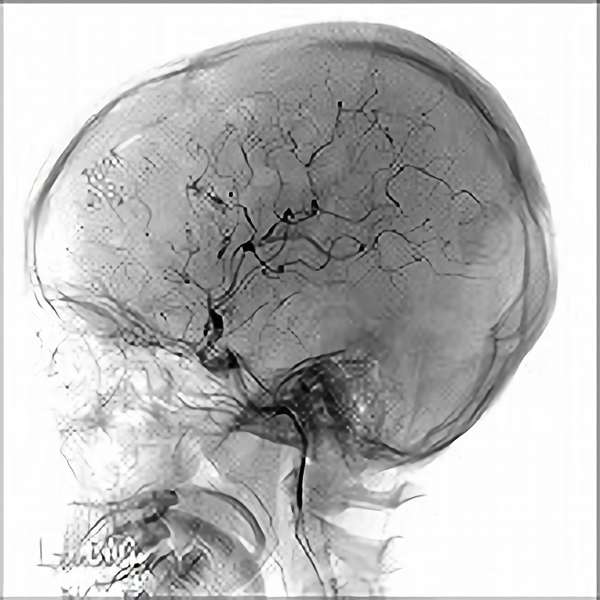

脳血管撮影

手術前

手術後